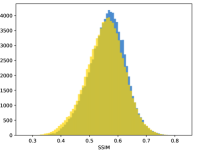

To visualise similarity metrics that compare image pairs (RMSE, SRE, SSIM) two metric distributions are generated: intra-similarity and inter-similarity. For each compared sample 300 random images are selected. The inter-similarity distribution is calculated for each image pair combination from both compared samples e.g. generated images of COVID-19 and real images of COVID-19. For the intra-similarity, all pairs of images in a single sample e.g real images of COVID-19 are considered. By comparing the shape of intra-similarity for the training subsample (Dataset) with the inter-similarity of training and generated samples the quality of the generated sample can be judged. It is also possible to compare in this way between the four image classes present in the dataset. The resulting distributions of inter-similarity of COVID-19 and the three remaining classes are compared in Fig. 4 to distributions of intra-similarity of the COVID-19 sample for each metric. All metrics, as expected based on available medical evidence Rubin et al. (2020), indicate that there are visible differences not only between COVID-19 and normal samples but also between viral pneumonia and lung opacity. Therefore, all classes should be distinguishable.

To visualise differences between synthetic and real samples distributions are generated for each of the RMSE, SRE and SSIM metrics: intra-similarity and inter-similarity. For each compared sample 300 random images are selected. The inter-similarity distribution is calculated for each image pair combination from both compared samples e.g. generated images of COVID-19 and real images of COVID-19. For the intra-similarity, all pairs of images in a single sample e.g real images of COVID-19 are considered. The distributions for generated samples describe very well the distributions for corresponding real images as shown in Fig. 6.

The quality of generated images is also confirmed with classical similarity metrics. The distributions of those similarity measures between generated and real images are compared for each sample with the distribution obtained within the real samples 6. The distributions for generated samples describe very well the distributions for corresponding real images. For an example see the results for the SSIM metric presented in Fig. 10. The small visible differences are almost insignificant compared to differences observed between the classes in Fig. 4.